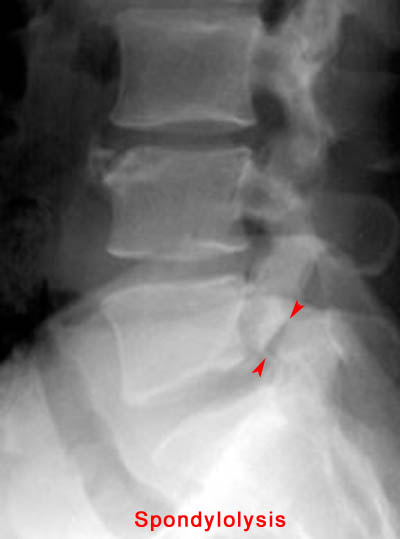

19) Name the abnormality shown in the image below.

20) In which demographic is the injury shown above most common? Adolescent Athletes

21) At which spinal level is the injury shown above most common? L5

22) Name the abnormality shown in the image below.